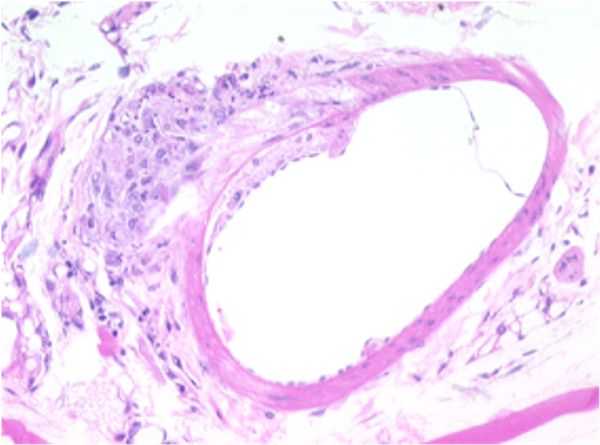

Thoracic Aorta

THORACIC AORTA: F18-01

Atherosclerotic plaque, tunica intima/media, thoracic aorta.

A focally-extensive area of the endothelium appears to be elevated off the tunica media by an accumulation of eosinophilic, lipoid, or foamy appearing material which occupies the subendothelial space between the tunica intima and the tunica media. There appears to be a focally-extensive disruption of the internal elastic membrane by the accumulation of eosinophilic, lipoid or foamy appearing material within the subendothelial space between the tunica intima and the tunica media.

An area of similar material accumulation also appears present opposite the sub-endothelial proliferation. The clear, vesicular spaces within the sub-endothelial material layer were considered representative of multiple, variably-sized cholesterol clefts. Also present within the area of foam cell accumulation was a mild infiltration of collagen and fibroblasts, representing early fibroplasia.

None of the arteries contain indications of either calcification or cellular necrosis, which is usually associated with atherosclerotic change in vessels. This absence may be representative of either a lack of lesion chronicity, or depicts how the lesion is presented in this animal model.